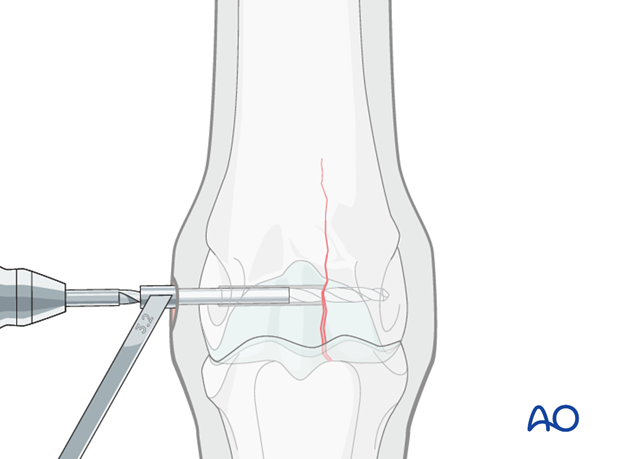

The 4.5 mm drill bit is removed, holding the drill guide in place. A 2.5 mm pin is placed through the drill guide into the glide hole.

The 4.5 mm drill guide is removed and the 3.2 mm drill guide is slipped over the 2.5 mm pin into the glide hole.

The pin is removed.